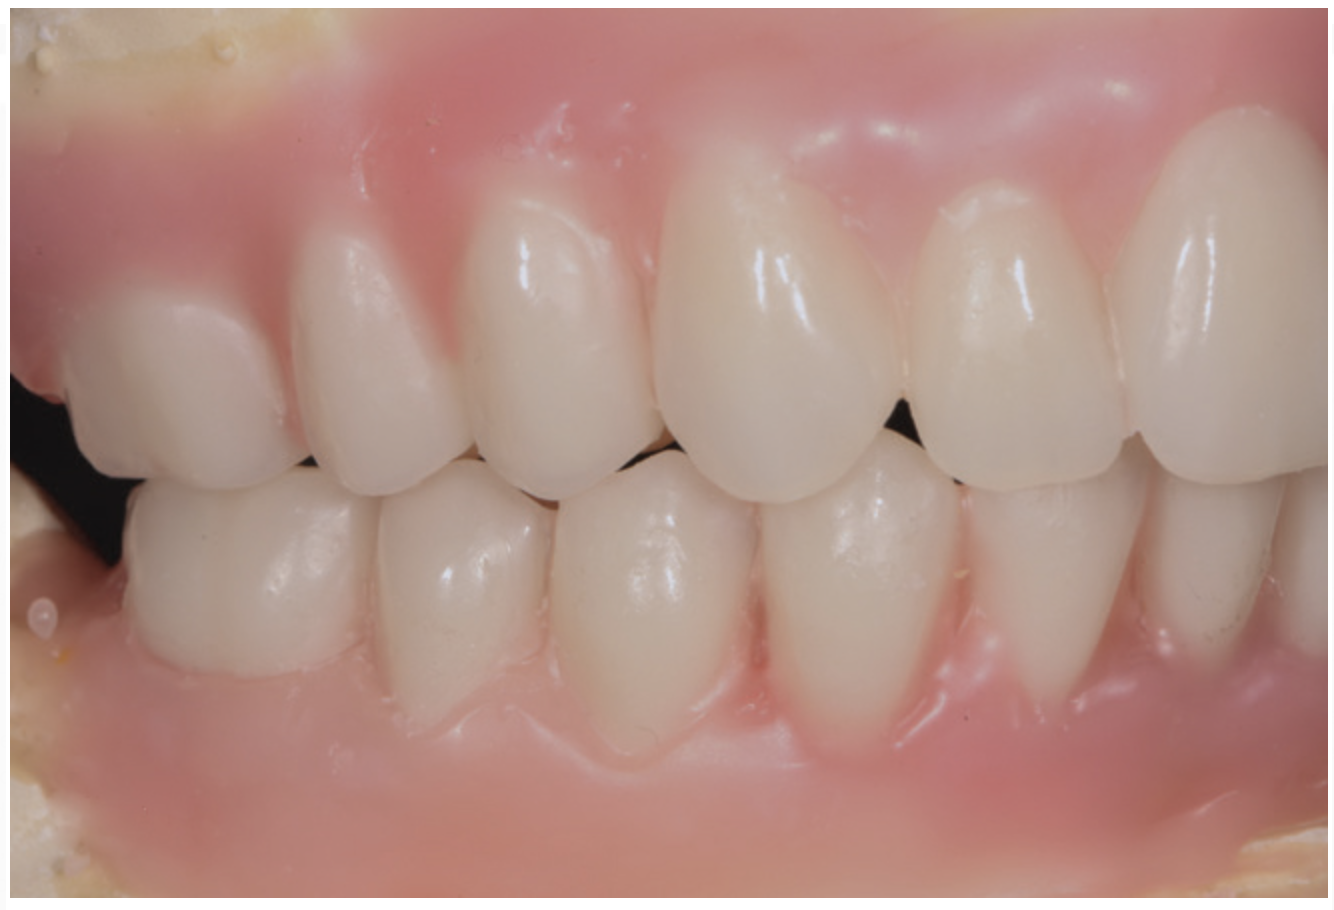

Fig 20. Patient intraoral condition 3 years following delivery of maxillary and mandibular All-on-4 definitive prosthesis.

Figure 20